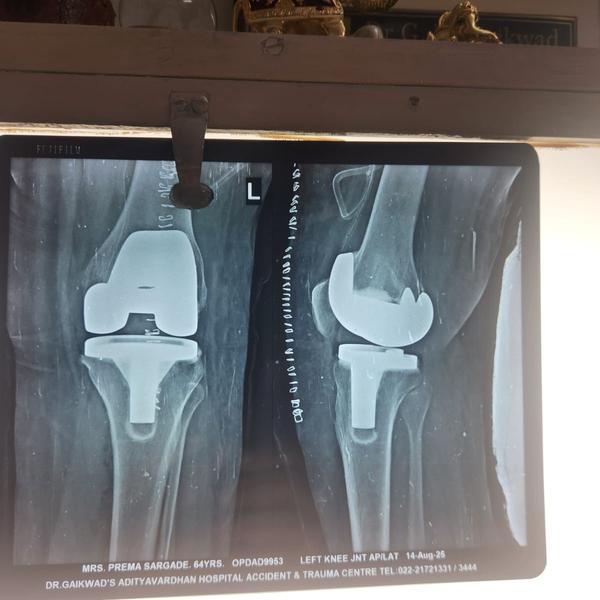

Robotic Knee Replacement Surgery in Thane

Knee replacement surgery in Thane